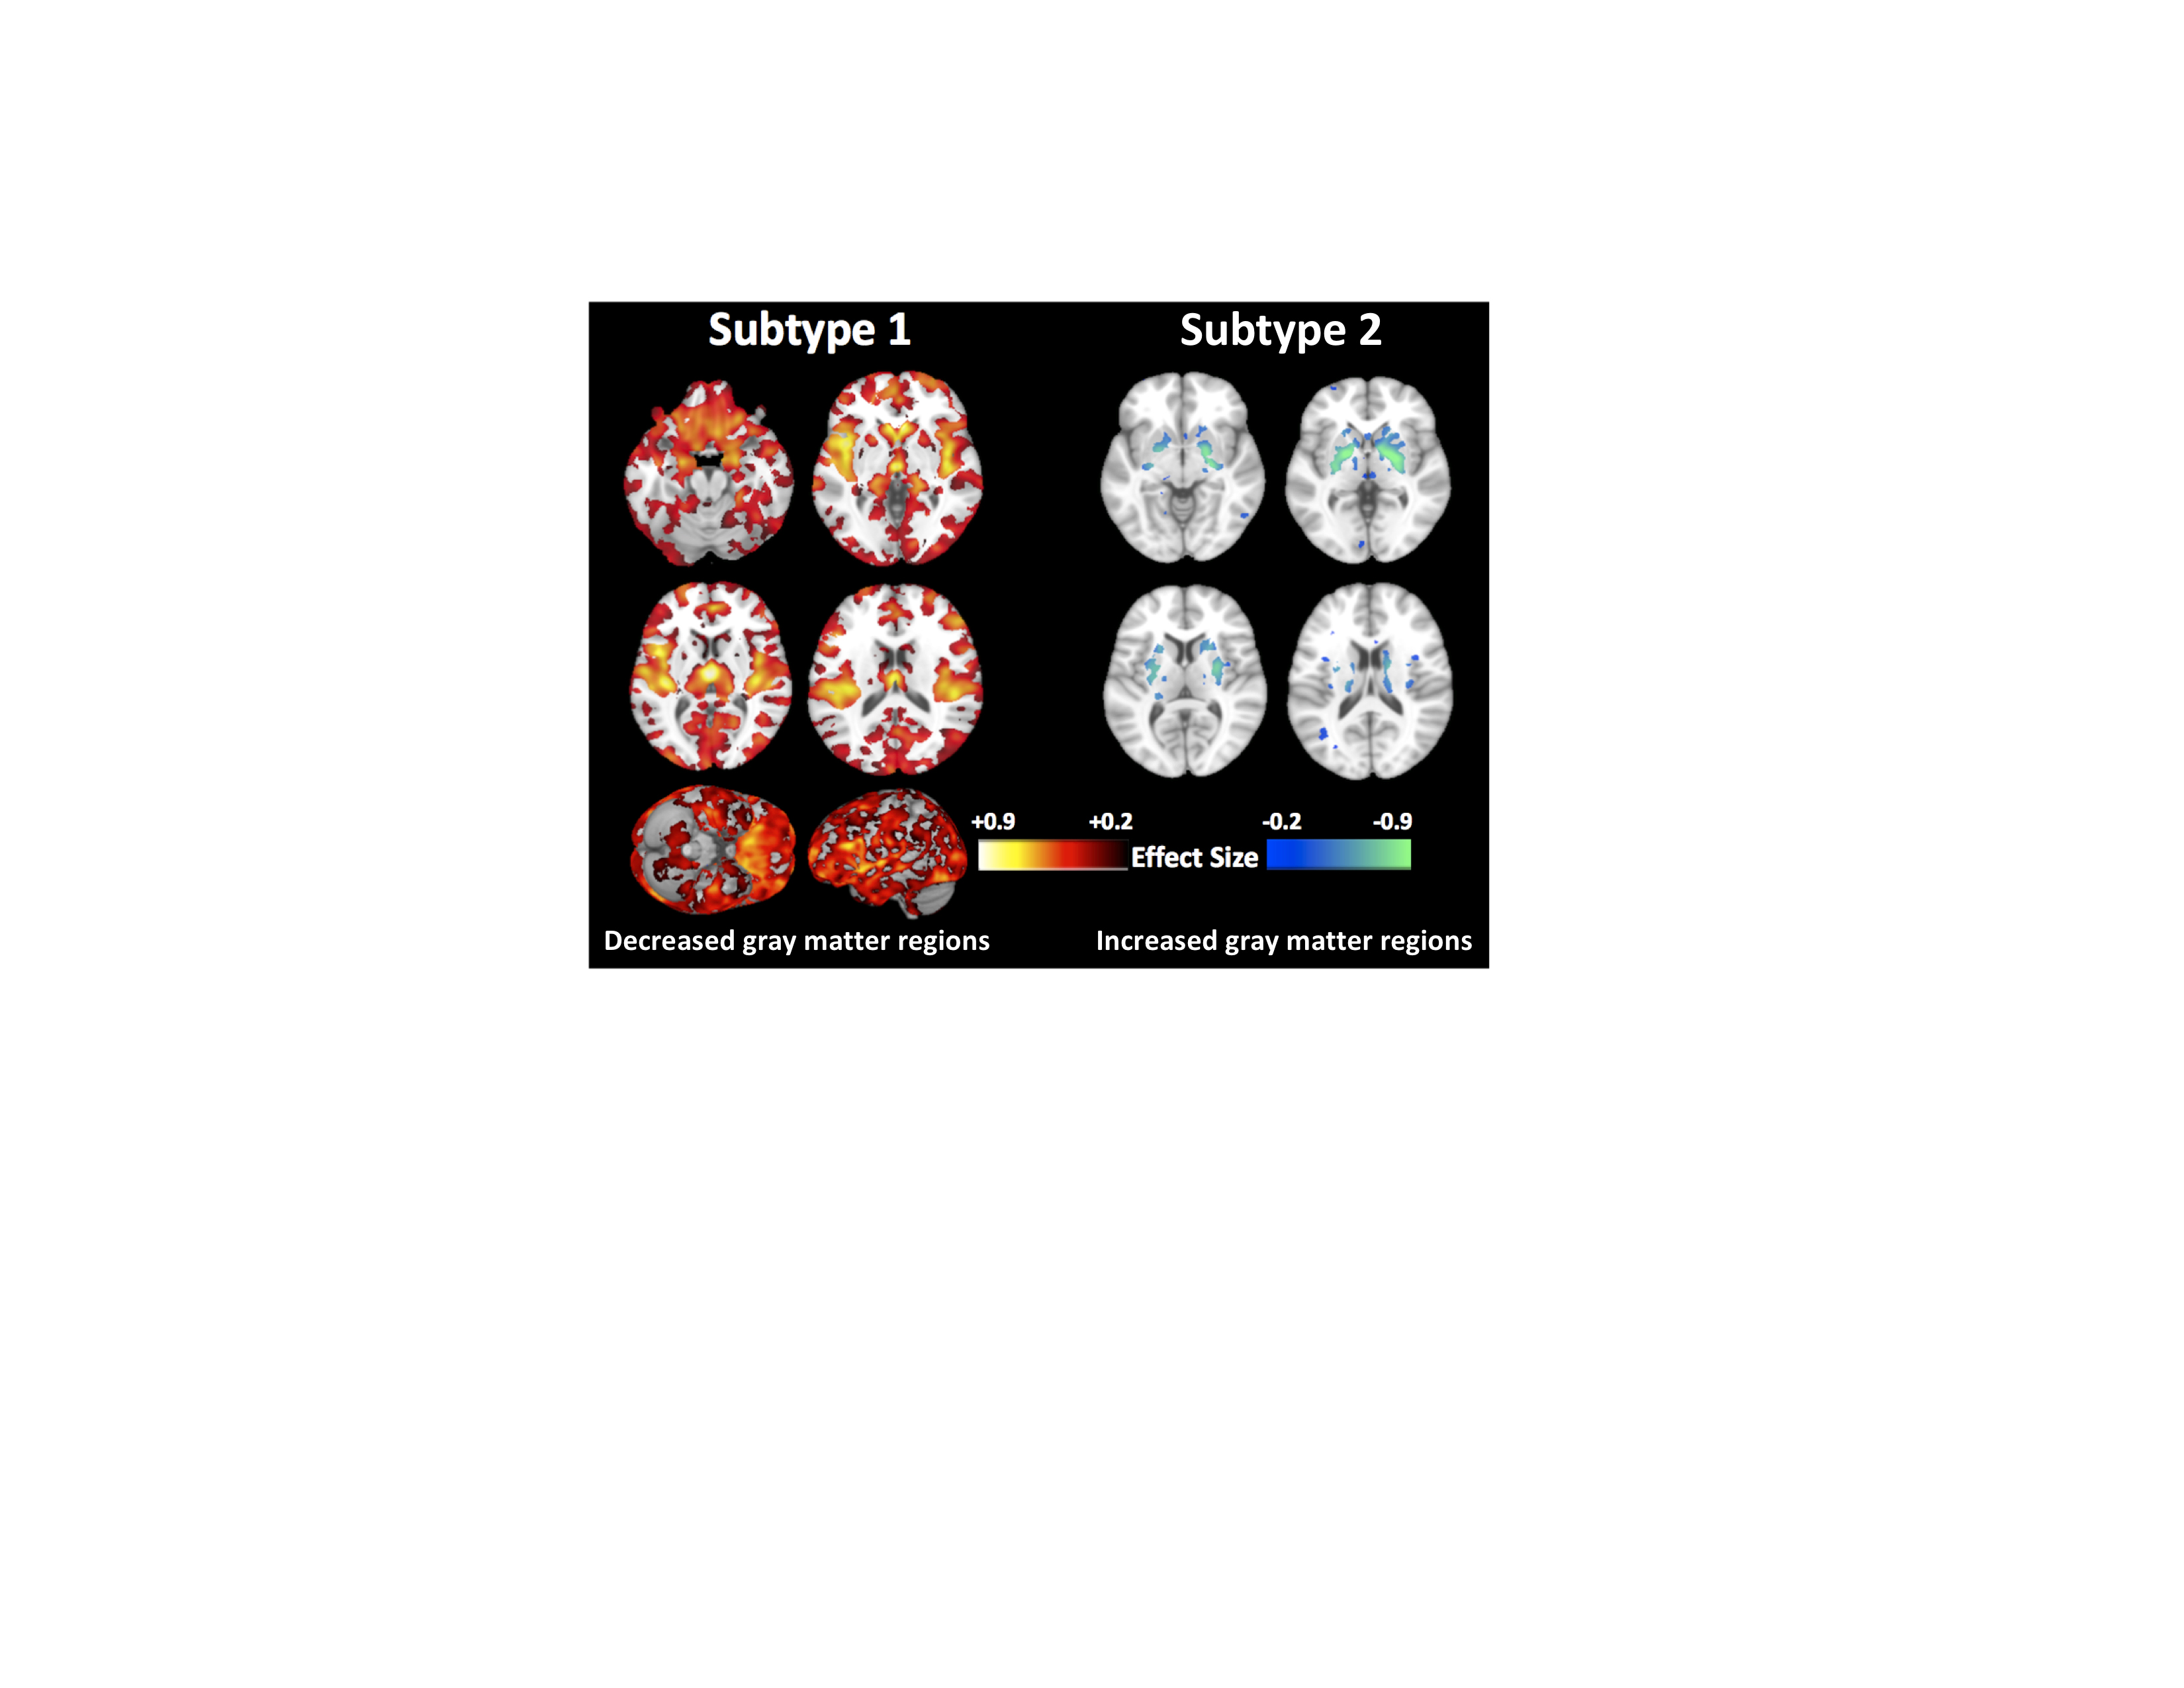

Descubren un segundo tipo de esquizofrenia que puede darse en cuatro de cada diez pacientes